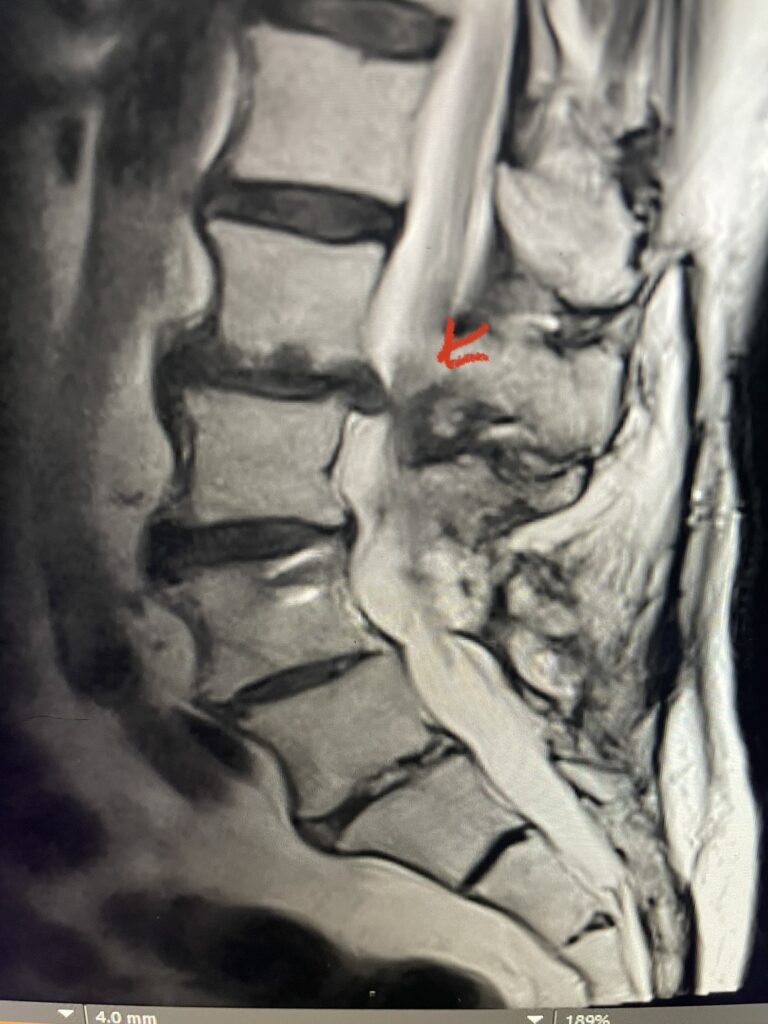

The spinal synovial cyst is one of the most interesting expressions of spinal instability. They emanate from the synovial lining of a degenerated facet joint that […]

People are obsessed with cysts! When you think about it, the body likes to form cysts. Why does this happen? Cysts can form just about anywhere […]